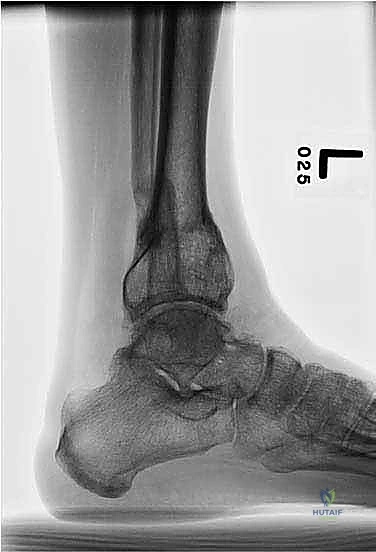

* أشعة سينية طولية للطرفين السفليين أثناء الوقوف (Standing Long-Leg X-rays): هذه هي الصورة الأهم. تسمح للطبيب برؤية محور الساق بالكامل من مفصل الورك، مروراً بالركبة، وصولاً إلى الكاحل.

فلسفة جراحة قطع العظم فوق الكاحل: لماذا هذا الموقع؟

كما ذُكر في الخلاصة الأولية، فإن اختيار مكان قطع العظم (Osteotomy Site) ليس عشوائياً. الفلسفة الأساسية التي يتبناها الجراحون الخبراء مثل الدكتور هطيف تعتمد على مبادئ بيولوجية وميكانيكية صارمة:

لماذا يتم القطع فوق الكاحل بحوالي 5 سم؟

1. الابتعاد عن العظم المتصلب (Sclerotic Bone): في نقطة التشوه القصوى (قمة التشوه الحقيقية)، غالباً ما يكون العظم كثيفاً جداً وضعيف التروية الدموية بسبب الإجهاد الميكانيكي المزمن. القطع في هذا المكان يؤدي إلى تأخر في الالتئام (Delayed Union) أو عدم الالتئام (Non-union).

2. استغلال منطقة الميتافيزيس الغنية بالدم: بنقل موقع القطع قليلاً إلى الأعلى (حوالي 5 سم فوق المفصل)، يتم القطع في منطقة ذات نسيج إسفنجي غني بالخلايا الجذعية والأوعية الدموية، مما يضمن التئاماً سريعاً وقوياً جداً وتكويناً ممتازاً للعظم الجديد (Regenerate Bone).

3. المساحة الكافية لتثبيت المسامير: يجب ترك مساحة كافية من العظم السليم بين مفصل الكاحل ومكان القطع لتثبيت أسلاك ومسامير المثبت الخارجي بقوة دون اختراق كبسولة المفصل.